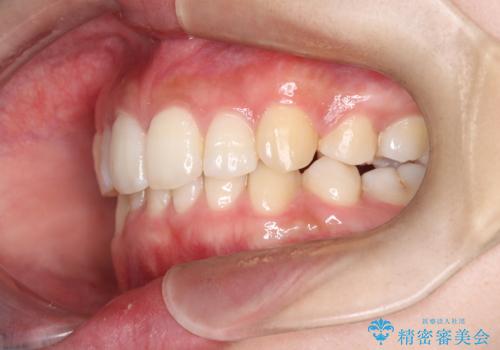

- 前歯から奥歯にかけて歯の重なりが激しい歯のがたつき(重度叢生)を主訴にご来院されました。精密検査の結果、歯が並ぶスペースが大幅に不足しており、歯並びを整え、口元を美しく引っ込めるためには、スペースの確保が必要と診断しました。そこで、上下左右の第一小臼歯(4番目の歯)を計4本抜歯し、そのスペースを利用して歯並び全体を整える抜歯矯正の治療計画を立案。装置には、透明で目立たないインビザラインを採用し、審美性と治療効果の両立を目指しました。

今回の治療では、重度の叢生を改善するため、まず計画通り上下左右4本の小臼歯を抜歯し、歯を並べるための十分なスペースを確保しました。装置には透明で取り外し可能なインビザラインを使用。抜歯によってできたスペースを最大限に活用し、マウスピースを定期的に交換しながら、デコボコを解消しつつ、前歯を効果的に後退させました。

治療の結果、長年の悩みであった重度の歯のがたつきが解消され、口元の突出感も改善。機能的にも安定し、審美的にも美しい、理想的な歯並びを獲得していただけました。